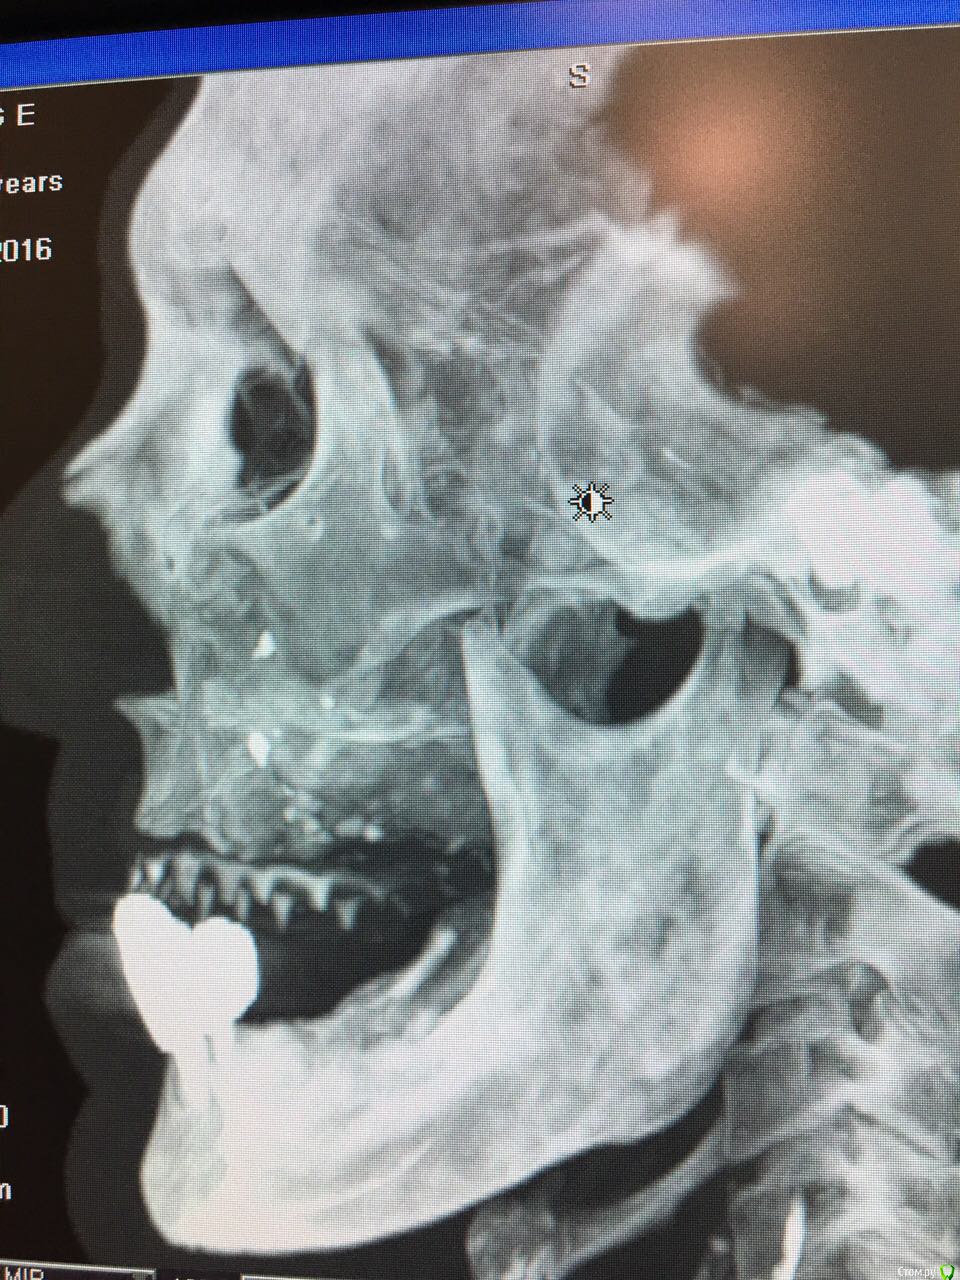

Kostoprav Опубликовано 17 августа, 2016 Поделиться Опубликовано 17 августа, 2016 знакомый рентгенолог прислал снимки, с его слов деформация лица почти отсутствует, пациента ничего не беспокоит.кто что думает? Ссылка на комментарий

Kostoprav Опубликовано 17 августа, 2016 Автор Поделиться Опубликовано 17 августа, 2016 вот еще Ссылка на комментарий